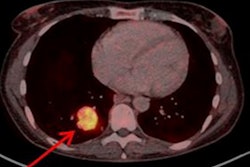

Maximum-intensity projection images with Cu-64 DOTATATE PET/CT are from a patient with metastatic bronchial carcinoid and extensive metastatic disease, including multiple small liver metastases (A). Corresponding CT image (B), PET (C), and fused PET/CT (D) show multiple bone metastases (yellow arrows). Images courtesy of JNM.Cu-64 DOTATATE prompted only a handful of minor adverse effects. Five (8%) of the 63 subjects reported a total of nine mild to moderate adverse events, with eight of those incidents deemed "probably" not related to the radiotracer. The complaints included one case each of nausea, headache, and fainting, along with two cases of vomiting.